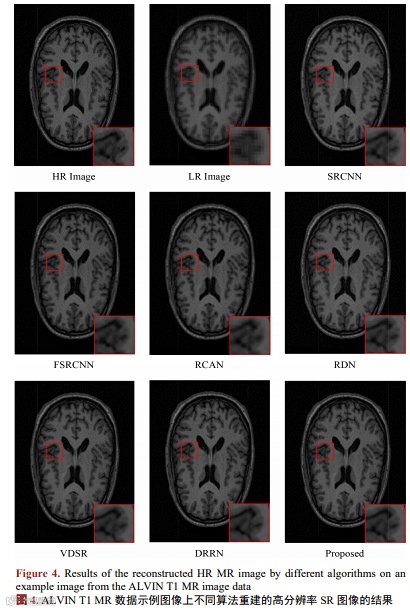

为了验证我们的方法对大脑核磁共振图像数据集的影响,将此方法与其他超分辨图像重建方法进行比较。为了保持对照实验的公平性,将网络深度较大的RCAN、RDN与DRRN中各自的模块个数减小,使其网络深度与本算法类似进行对比实验。在这项工作中,我们提出了一种新的基于多尺度残差学习和正则化的超分辨算法,用于核磁共振图像的重建。基于三个真实MR图像数据集的结果显示,本文提出的算法优于其他超分辨算法。

本文我们提出了一种改进的深度学习超分辨网络,通过使用多尺度残差模块以及正则化项的创新,来提高算法在临床大脑核磁共振图像超分辨重建任务上的准确率。此算法可以有效地重建大脑核磁共振图像的细节信息,通过在三个临床MR图像数据库上的实验结果表明,在没有增大算法复杂程度的情况下,本文提出的算法性能优越,与目前先进的超分辨算法相比有显著的提升。